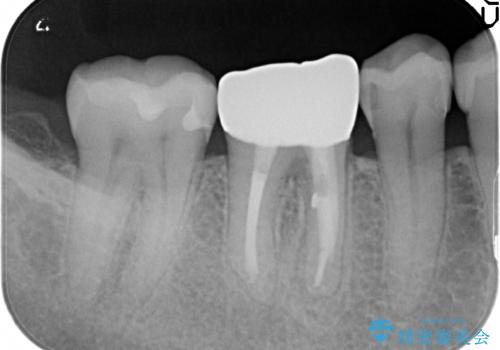

咬んだ時の違和感 顕微鏡で発見された歯の穴を処置し、かみ合わせを回復する

- 再根管治療にて発見されたパーフォレーションを修復し、改めてかぶせ物を製作する。

レントゲンに大きな問題がなくても、実際に顕微鏡で見ることにより様々な問題が露呈することはよくあります。

再治療の繰り返しにより歯に穴があいてしまっていることもよくありますが、このような深い位置の穴は、特殊なセメントで封鎖することにより非常に経過良く処置することができます。